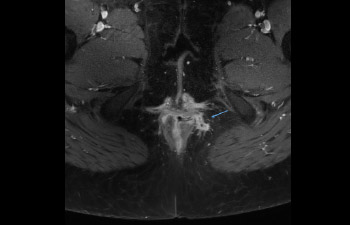

Pelvis con fístula